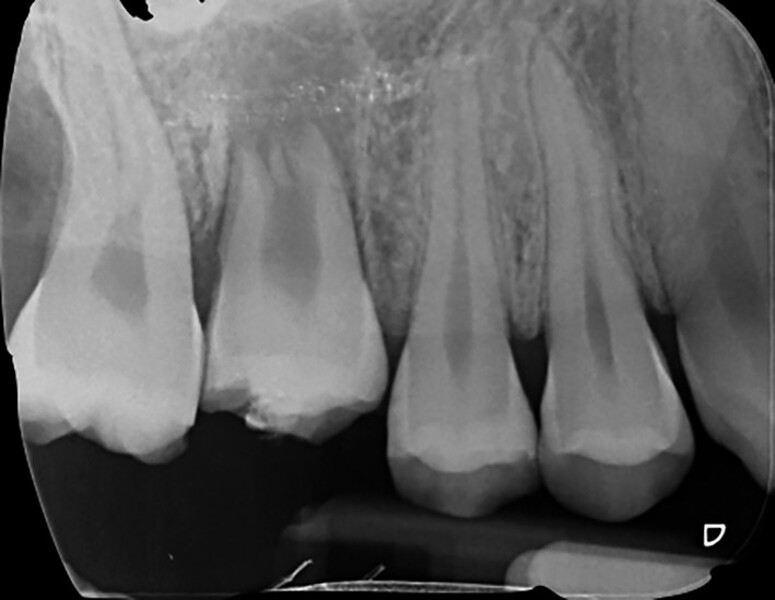

Fig. 16a: Pre-op periapical radiograph.